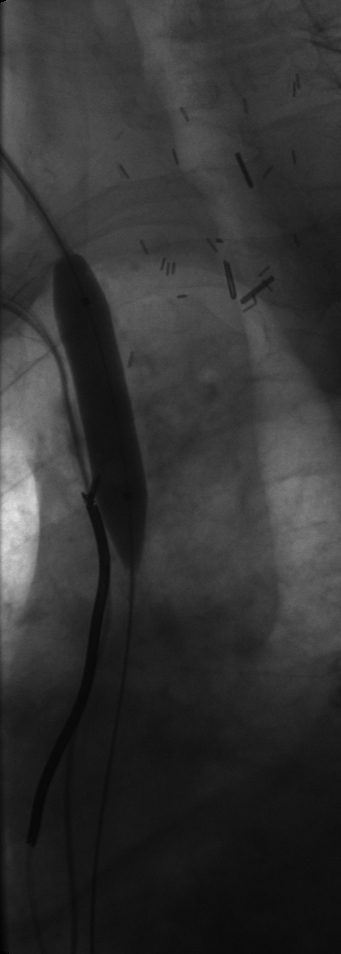

Late-phase balloon inflation: Complete dilation of the central veins.